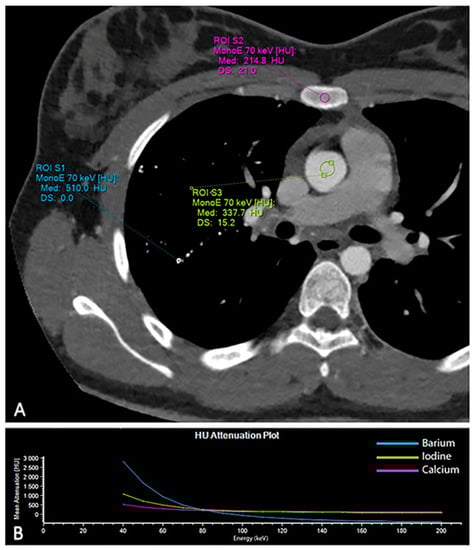

Multi-Contrast Differentiation by Dual-Energy Spectral CT Angiography in a Patient with Pulmonary Barium Granulomas

2. Case Report

3. Discussion